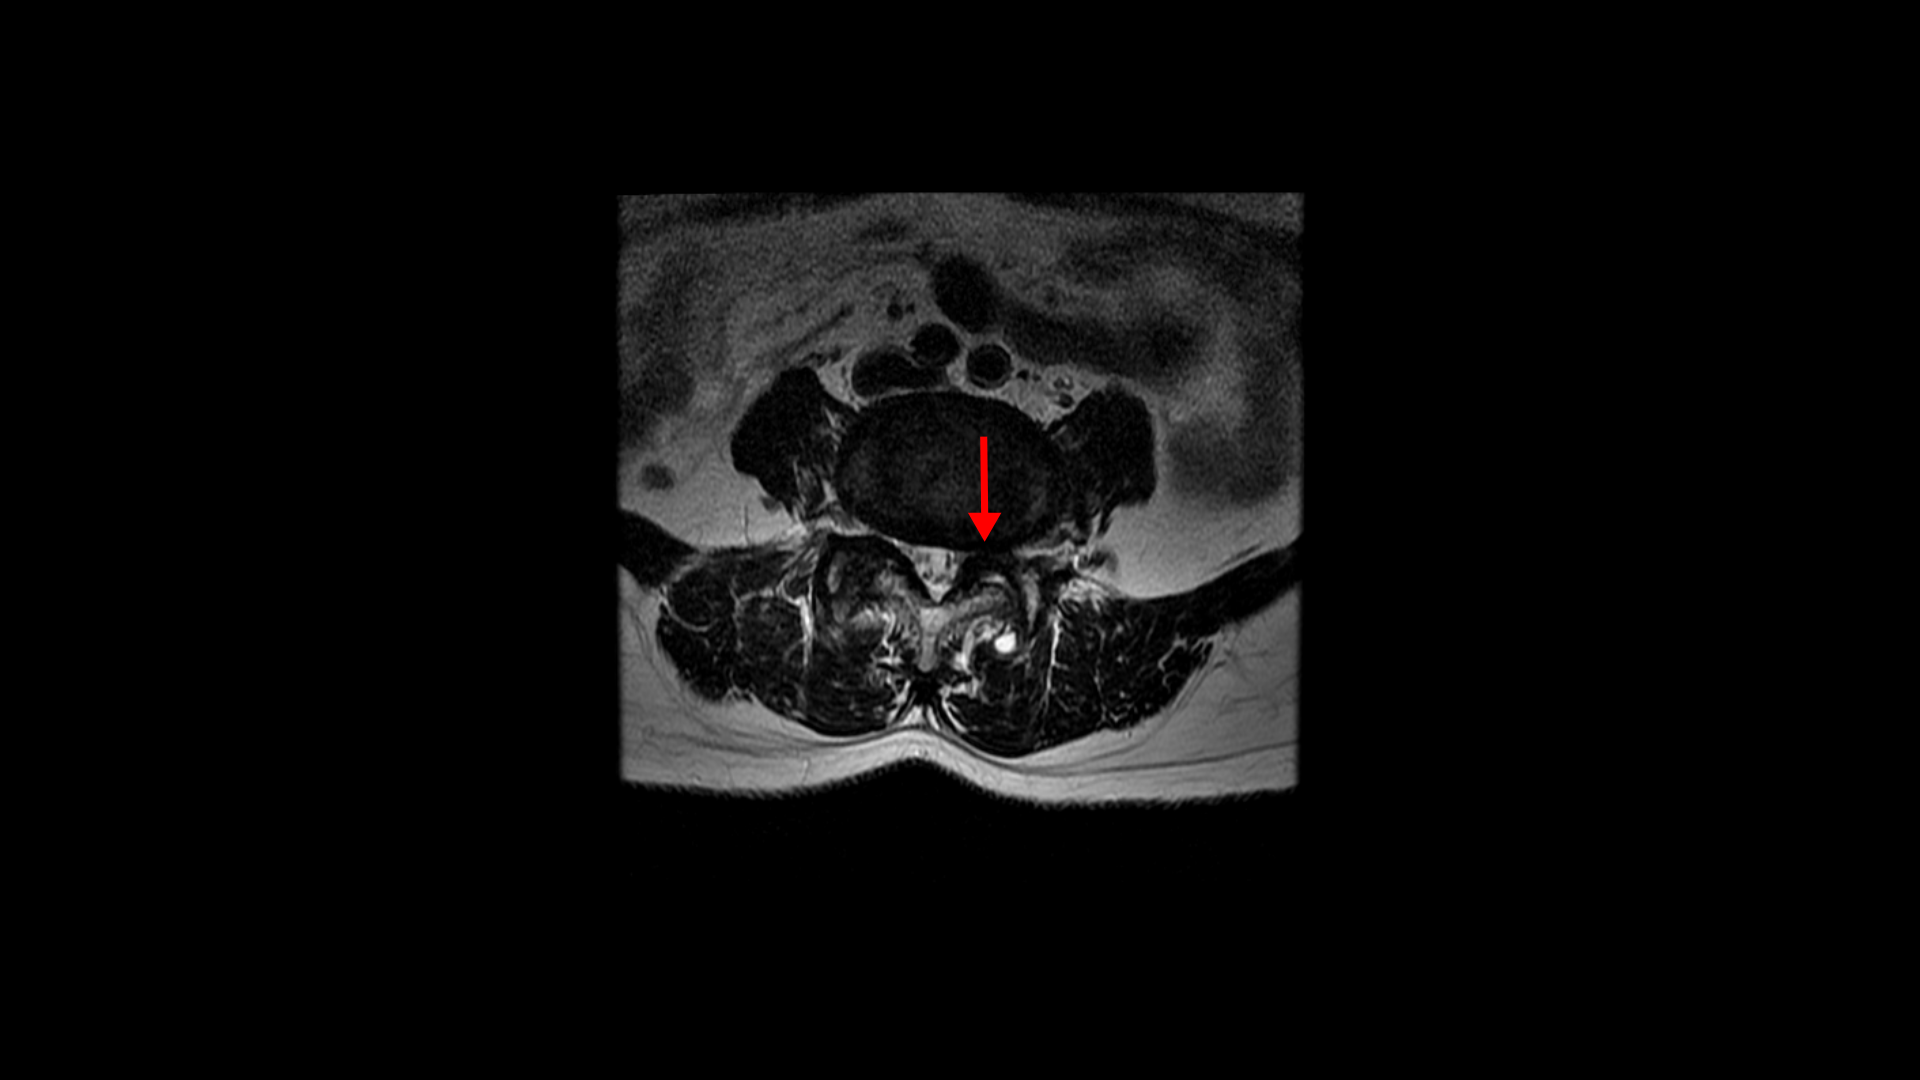

우선 이 환자분의 MRI를 함께 보겠습니다. 이 환자분의 척추에는 3번 4번과 4번 5번에 각각 1단계의 전방전위증이 있습니다.

중심성 협착도 있습니다.

그리고 중심성 협착도 있습니다.

그런데 이 환자분의 제일 불편한 증상은 왼쪽이 아니고 오른쪽 엉치와 다리 증상입니다. 이분 오른쪽 신경 구멍들을 보면 전부 다 넓게 잘 열려 있습니다.

엉치와 다리 방사통을 일으킬만한 특별한 신경 눌림이 보이지 않는 것입니다. 그럼에도 불구하고 여러 마디의 전방전위증과 척추관 협착 그리고 디스크 탈출이 있으니까 그것을 원인으로 보고 신경 주사도 맞고 시술도 받으셨습니다. 그러나 별 효과는 없었습니다. 그리고 대학병원에서도 결국은 수술밖에 방법이 없다고 수술을 권유하였습니다.